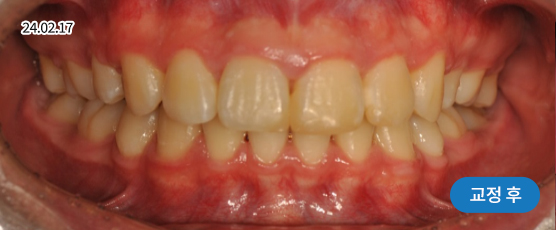

* 본 사진은 동일 조건에서 촬영되었으며, 환자 본인의 동의를 얻어 게재되었습니다.